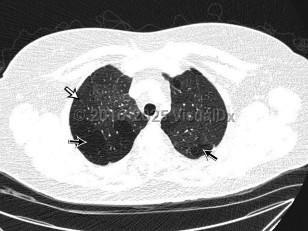

Bronchiolitis obliterans

The clinical syndrome manifests as an airway obstruction, cough, and slowly progressive dyspnea (weeks to months), with radiographic examination showing normal or hyperinflation of the lungs. Tachypnea, crackles, and/or wheezing may be evident on physical examination.